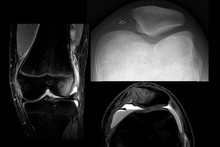

| Radiograph of a patient with patellar dislocation. Normally the patella projects over the distal femur. | |

Patellar dislocation is an injury of the knee, typically caused by a direct blow or a sudden twist of the leg.[1] It occurs when the patella (kneecap) slips out of its normal position in the patellofemoral groove, and generally causes intense pain with swelling of the knee.[1] Open or arthroscopic surgery may be used to repair damage, but are typically avoided since rates of re-injury, knee function, and patients' opinions do not differ much from conservative treatment.[2][3][4]

To assess the knee, a clinician can perform the patellar apprehension test by moving the patella back and forth while the patient flexes the knee at approximately 30 degrees.[6]

The patient can do the patella tracking assessment by making a single leg squat and standing, or by lying on his or her back with knee extended from flexed position. A patella that slips medially on early flexion is called the J sign, and indicates imbalance between the VMO and lateral structures.[14]